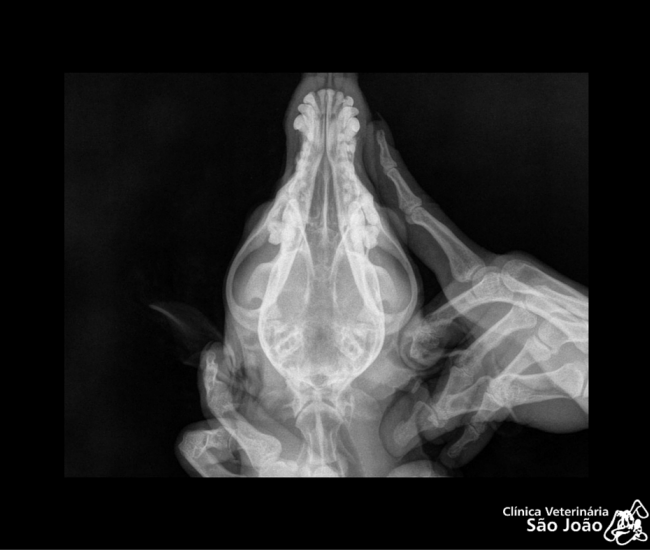

- Diferentemente do raio-x analógico, este raio-x oferece altíssima definição e todas as vantagens da tecnologia digital. É possível aproximar a imagem, trabalhar o contraste, exposição.O software permite ainda avaliações da medida cardíaca do animal e graus de displasia coxofemoral, por exemplo – explica o Dr. Nardeli Lucena.

O serviço também é realizado pelo médico veterinário Alessandro Nora Lucena, especializado em diagnóstico por imagem, nas áreas de ecografia e radiologia.